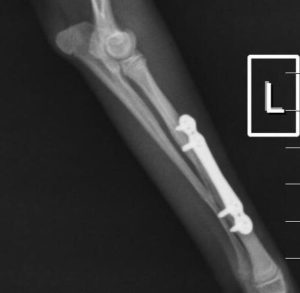

În cazul raselor de talie foarte mică, cunoscute drept “toy breeds”, fracturile de radius și ulnă constituie o categorie aparte de traumatisme ortopedice. Vascularizația redusă la acest nivel face ca aceste oase să fie vulnerabile chiar și în urma unor accidente minore – o săritură din brațele proprietarului sau de pe mobilier poate fi suficientă pentru a produce o fractură completă.

Tratamentul acestor leziuni este delicat, deoarece diametrul osos este extrem de redus, iar stabilizarea trebuie realizată cu maximă precizie. În prezent, dispunem de implanturi ortopedice de ultimă generație, concepute special pentru pacienții sub 2 kg, care permit stabilizarea sigură și eficientă a oricărui tip de fractură.

Pentru aceste rase, un pas esențial în managementul postoperator îl reprezintă extragerea implanturilor după confirmarea radiologică a vindecării osoase. Eliminarea acestora reduce riscul de resorbție osoasă și contribuie la menținerea unei integrității structurale optime pe termen lung.

Intervențiile sunt realizate cu anestezie inhalatorie și tehnici de blocaj loco-regional, ceea ce diminuează semnificativ nivelul de durere resimțită de pacient atât în timpul intervenției, cât și postoperator.

Astfel de situații demonstrează cât de mult contează echipamentele adecvate, experiența echipei și un protocol bine stabilit pentru a obține o recuperare completă și sigură.